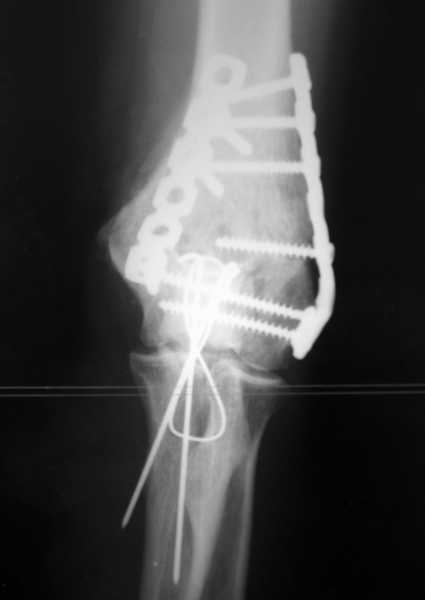

У пациентки 42 лет после операции остеосинтеза чрезмыщелкового перелома плеча, выполненной в нашей клинике 2 месяца назад, на контрольных R-граммах имеется гетеротопический оссификат по передней поверхности плеча. Оперирована по методике АО, после операции максимально рано начала заниматся ЛФК. В настоящее время основная жалоба пациентки на ограничение сгибания в локтевом суставе. Клинически объем движений: сгибание 90 градусов, разгибание 170 градусов, ротационные движения в полном объеме. Привожу снимки сразу после операции и через 2 месяца. (На рентгенограммах после операции в мягких тканях по передней поверхности плеча имеется небольшой костный фрагмент, но его ширина во фронтальной плоскости не более 1 мм., обнаружен был по снимкам после операции. Интраоперационно основные крупные фрагменты отрепонировались хорошо, объем движений был сгибание до 75 градусов, разгибание 175 град.) Пациентка неудовлетворена объемом сгибания, хотя была предупреждена о высокой вероятности ограничения движений. Профилактика гетеротопической оссификации (прием индометацина) не проводилась, т.к. имелась язвенная болезнь, да и эффект от его приема считаю сомнительным. Вопросы: 1.Стоит ли вмешиваться и пытаться удалить экзостоз? Если да,то в какие сроки и каким доступом лучше идти? 2. Оставить все как есть? 3. Не поможет ли ударно-волновая терапия либо какая-то другая методика? Буду благодарен за все ответы и оценки своей работы. С таким осложнением столкнулся впервые.

Снимки сделаны по правилам укладки, но объем сгибания сейчас 90 градусов. Пациентка хочет большего объема сгибания.